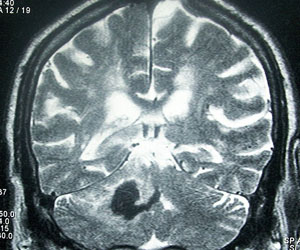

In May 2006, medical regulators in Denmark issued a warning that signaled trouble for General Electric. Danish researchers noted that, over a four-year period, 25 patients in Denmark and Austria had suffered a rare and crippling disease after undergoing an MRI, the scanning procedure used to diagnose everything from brain tumors to blown knees. The patients had been injected with a GE dye that makes images more distinct. They all had weak kidneys before receiving the dye.

The GE product, Omniscan, has since been linked to other cases of the disease, which appears to affect only MRI patients who have kidney problems. Similar drugs made by Bayer and others have also been tied to the sometimes fatal ailment, nephrogenic systemic fibrosis (NSF).

While GE says it is investigating concerns about Omniscan, the company maintains there is no proof that the drug, known as a contrast agent, causes disease. “NSF is a complex disease with a number of contributing factors,” GE said in a February 2009 position paper. It conceded that a critical ingredient in Omniscan and other agents may be one of those factors, “but not necessarily an essential” factor. Scientists concur that they don’t fully understand how the disease starts, although nearly all cases have involved patients with kidney problems who were injected with MRI contrast agents.

Omniscan and comparable products contain the potentially toxic metal gadolinium. During MRIs, the metal helps physicians see the brain and other parts of the body. Healthy kidneys filter out gadolinium. But patients with severely impaired kidneys can become victims of NSF, according to the FDA.

NSF starts with painful swelling in the legs and arms. It progresses to lesions in the skin and connective tissues, and it can attack organs, causing death. So far, there is no cure.

The FDA, meanwhile, was receiving an increasing number of reports of NSF, records show. In 2007 two agency doctors raised concerns about Omniscan. The FDA assigned Dr. Melanie Blank, a kidney specialist, to review the safety of all contrast agents. Blank’s report concluded that an “undeniable and strong association” existed between contrast agents containing gadolinium and NSF. In an interview, she said she found that medical and sales data indicated Omniscan “had most of the cases and less of a share of the market, so I believed Omniscan was the worst player.”

Another FDA staff member, Dr. Louis Marzella, did a separate review of Omniscan. In an April 6, 2007, report, Marzella said “a contraindication for Omniscan is warranted” for patients with severe kidney disease. A contraindication has the effect of banning certain uses of a drug, regardless of the possible benefits.